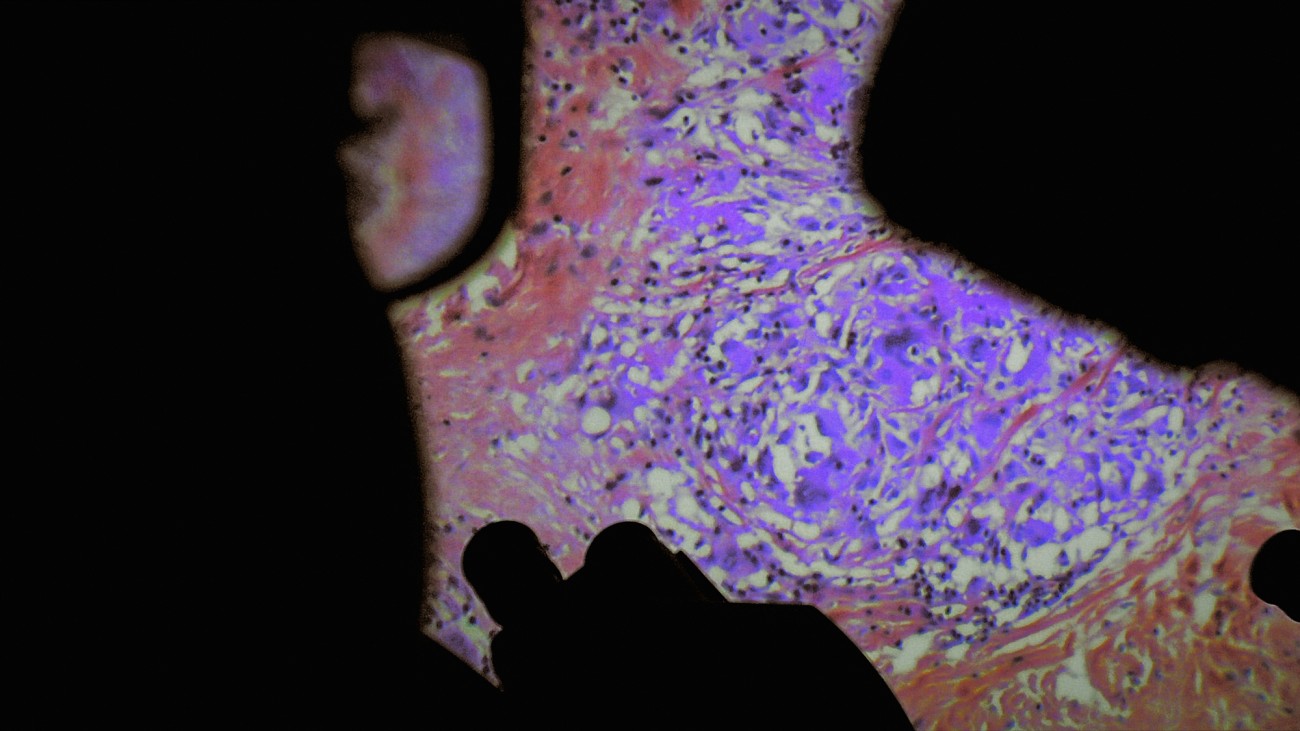

Reprenant le titre d’un traité d’anatomie du XVIe siècle, «De Humani Corporis Fabrica» s’intéresse à ce qui se passe non pas à l’intérieur de l’hôpital mais à l’intérieur des patients. Aux liens qui unissent le corps médical aux corps défaillants, fracassés, au bord de l’extinction. Il y a cinq siècles l’anatomiste André Vésale ouvrait pour la première fois le corps au regard de la science. «De Humani Corporis Fabrica» ouvre aujourd’hui le corps au cinéma. On y découvre que la chair humaine est un paysage inouï qui n'existe que grâce aux regards et aux attentions des autres. Les hôpitaux, lieux de soin et de souffrance, sont des laboratoires qui relient tous les corps du monde…